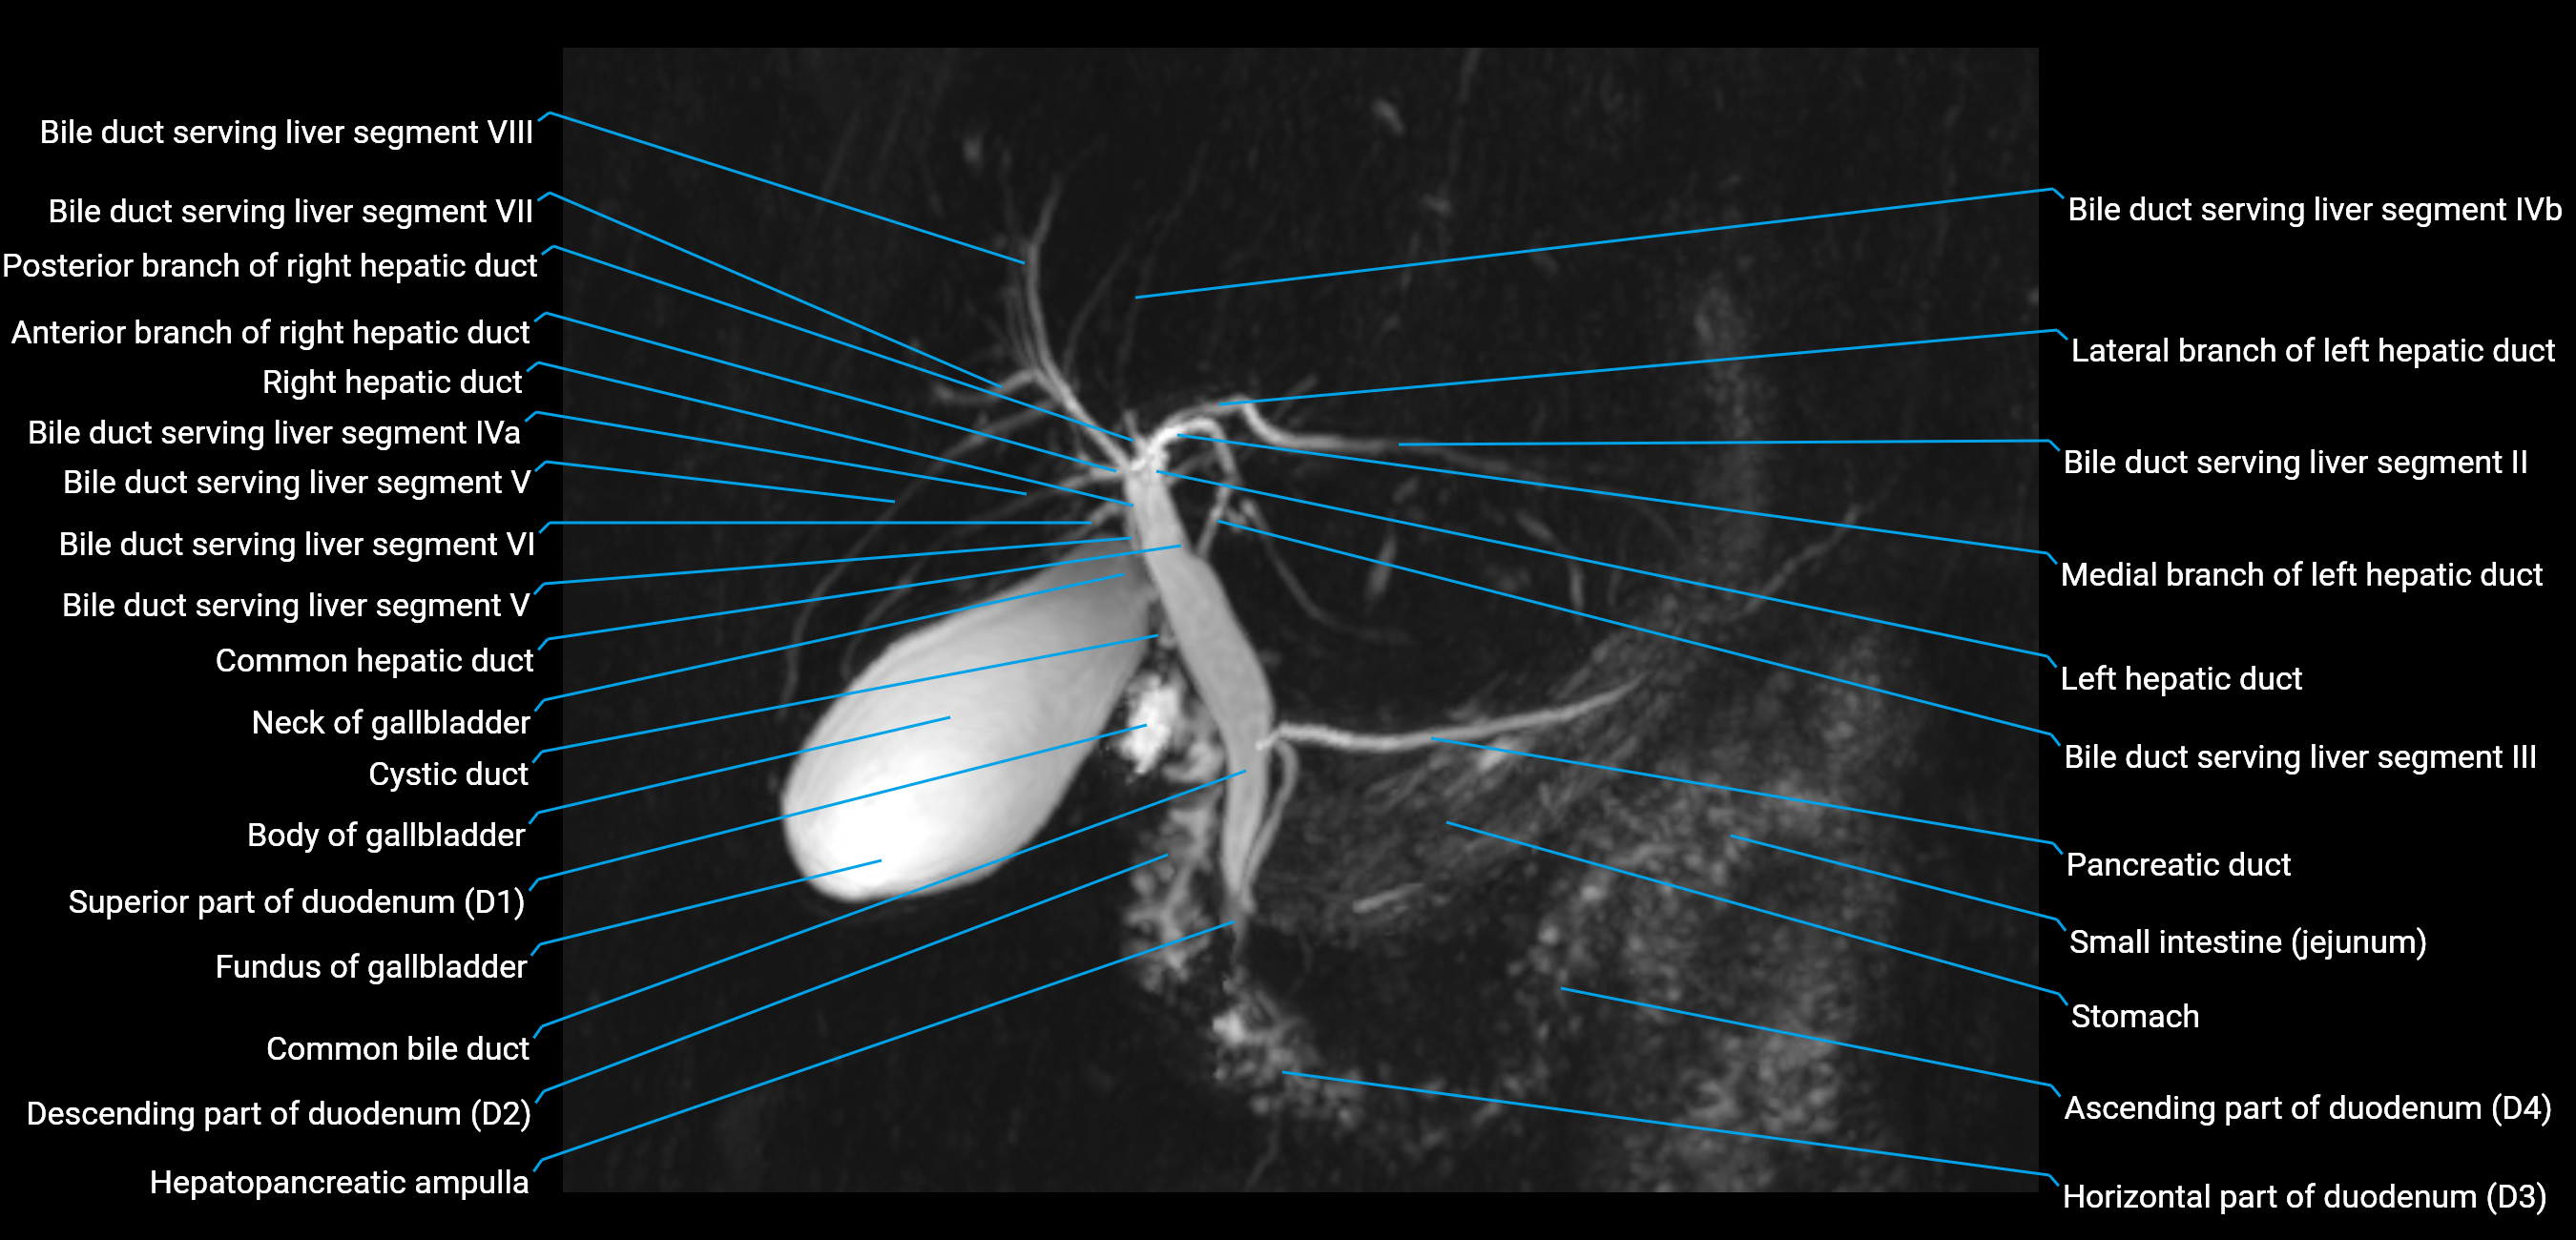

T2 TSE Fat-Saturated 3D (MRCP sequence):

• Duct visualized as a continuous bright tubular structure joining or parallel to the main pancreatic duct

• Allows 3D reconstruction of ductal anatomy and variants

• Excellent for diagnosis of pancreas divisum

Thick-slab T2 Fat-Saturated HASTE:

• Shows the accessory duct as part of the biliary–pancreatic system in a projectional image

• Highlights communication with main pancreatic duct and opening into the minor papilla

• Filling defects (stones, strictures) seen as dark spots within bright fluid

MRI image

image